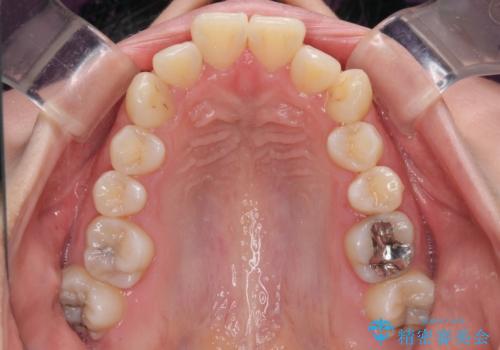

- 口元の突出感を気にして来院された患者様です。

口元を積極的に引っ込めるために、上下左右の第一小臼歯を4本抜歯することとし、ワイヤー装置による矯正治療を行うこととしました。

上下前歯がくちばしのように突出していましたが、抜歯矯正により口元が引っ込み、唇が閉じやすくなり、鼻の下の膨れた感じも解消されました。